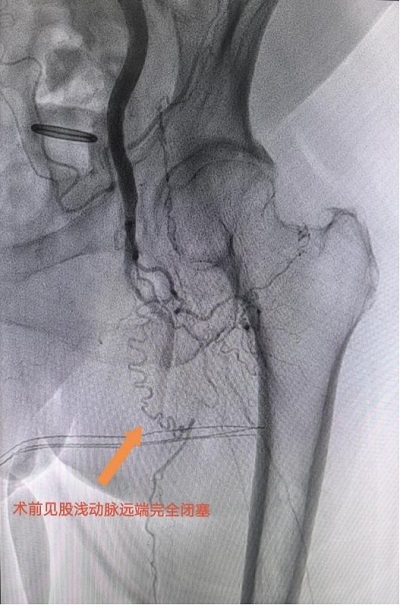

“結合病史和體征,我們高度懷疑下肢動脈硬化閉塞癥?!碧撇┱{出影像檢查報告,果然如他所想,結果顯示李曉蕓左側股淺動脈至腘動脈完全閉塞,血管遠端僅存一根頭發絲粗細的供血通道,動脈壁鈣化嚴重且布滿血栓,宛如一段廢棄的枯河。

患者左腿動脈血管閉塞嚴重。重醫附屬大學城醫院供圖

“這是典型的下肢動脈硬化閉塞癥晚期?!碧撇┙忉尩?。由于患者病變范圍從大腿根部蔓延至腳趾,動脈硬化程度嚴重到無法通過影像精準定位,加上82歲高齡及較差的肺功能,無法耐受全身麻醉,如要進行手術則風險極高。